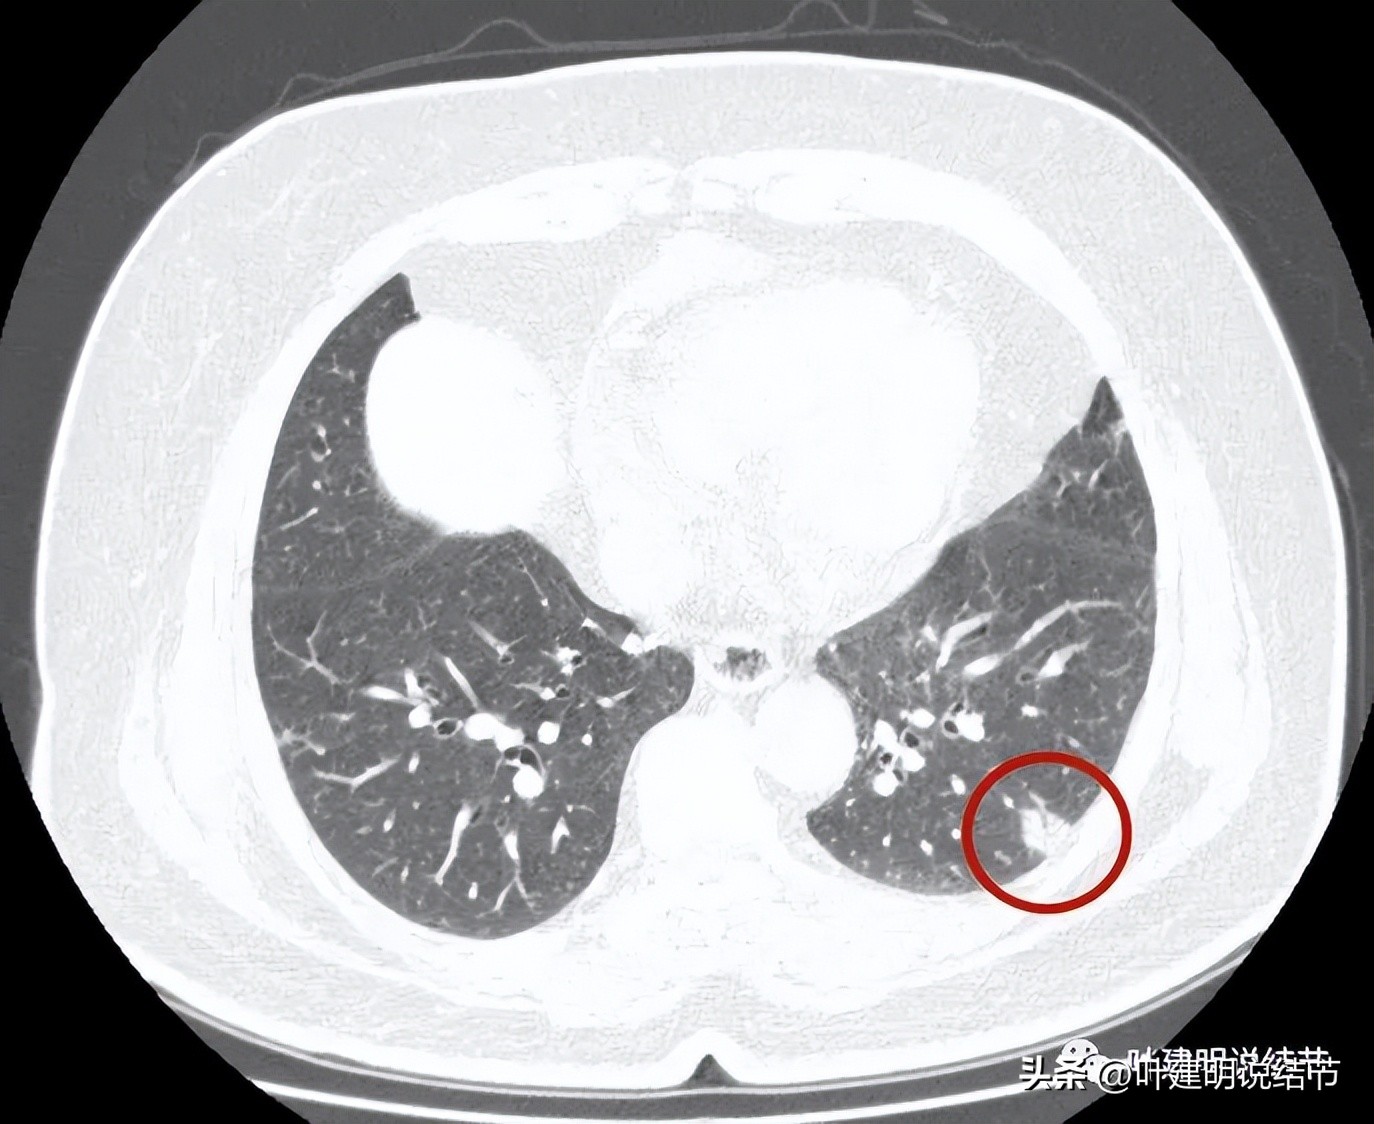

病灶4:左下叶实性结节,即主病灶,实性不是很致密的病灶,胸膜下,边界较清,邻近胸膜没有牵拉。有恶性可能性(良性的用什么疾病能解释?好像错构瘤、硬化性血管瘤、结核、肉芽肿性炎、淋巴结、急性炎症、隐球菌等常见的都靠不太上)。

病灶4:见有血管进入病灶,整体上是偏实性的,但感觉不太致密

左下叶的病灶单看真不能除外恶性,因为表面不平整,是磨玻璃偏实性的密度,整体轮廓也较清,内部密度不均,似乎还见血管征。但我们发现两肺胸膜下多发实性的微小结节,基本上都考虑是良性的,比如纤维增生结节或胶原结节可能性大,左上叶有处磨玻璃结节偏长条状,有局灶的细支气管扩张,给人的感觉是细支气管扩张伴周围慢性炎症,不是很像肿瘤。那么当两肺有这么多是炎症相关的结节时,左下主病灶会不会也是炎性的呢?显然这种概率就比较大了。其实将主病往炎性方面考虑也有许多依据的:边缘略显模糊,瘤肺边界不太清、血管进入没有增粗,也较单一;与胸膜贴近,但没有牵拉凹陷;病灶内部密度不密实,分叶或膨胀感也不明显。假如我们先撇开最后良恶性不讲,这个病灶目前应该不是典型的恶性,真恶性,也至少不是高危亚型(实体型或微乳头这种很实的密度的),大概率会是腺泡型之类,适当的随访观察应该不至于耽误病情,也不太会影响预后。所以我的想法是再过3个月复查靶扫描看看细节再说。